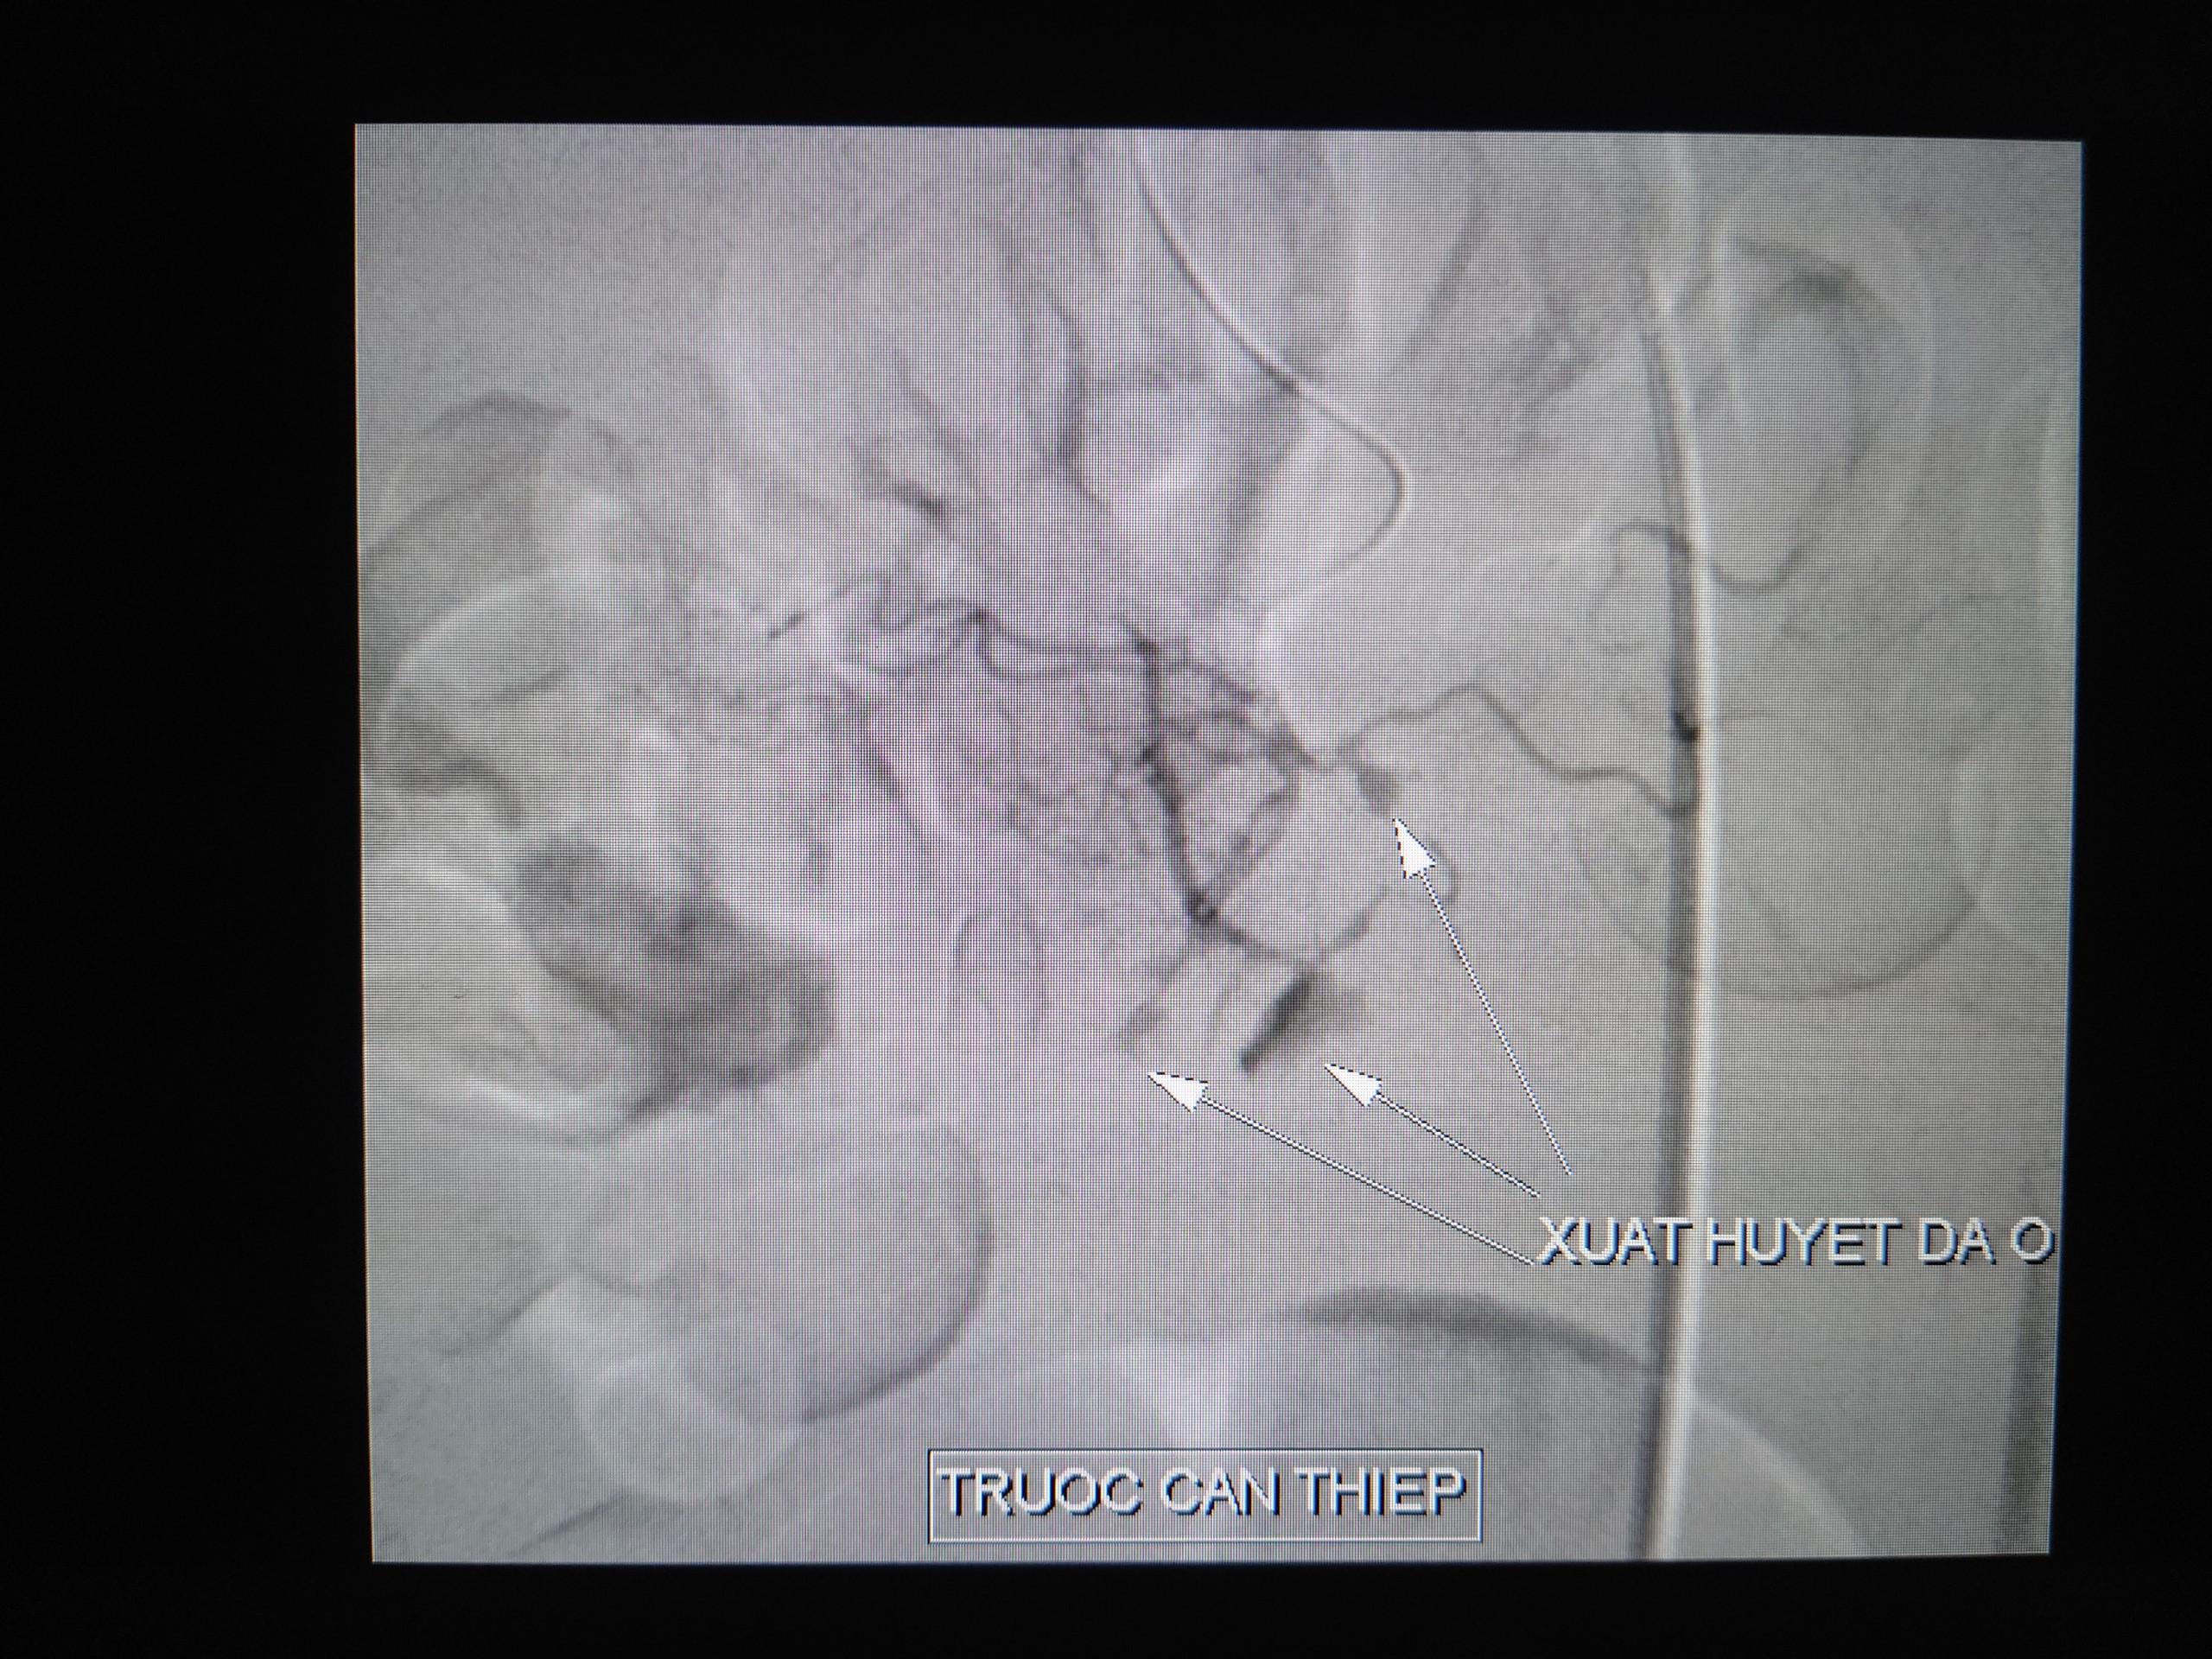

![]() |

Xuất huyết đa ổn do vỡ phình động mạch vị tá tràng |